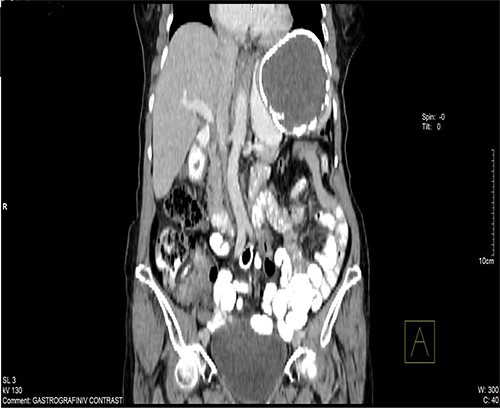

A 74-year-old woman was admitted to the internal medicine ward due to cough, pain and heaviness in the left upper abdominal quadrant. Pain was localized to the left upper abdominal quadrant, and it intensified within the last 2 months. The laboratory test results were normal. However, physical examination revealed tenderness upon palpation in the left upper quadrant and splenomegaly. Moreover, thoracic and abdominal radiography revealed an egg shell-like calcified well-circumscribed ovoid mass at the left upper abdominal quadrant (Fig. 1). Computed tomography (CT) scan of the abdomen revealed a 10.5 × 9.6 × 9.5-cm ovoid splenic cyst with peripheral rim calcification. The cyst had homogeneous internal substance with no prominent daughter cysts or scolices (Fig. 2). Thoracic and abdominal CT-scan did not reveal other pathologies and cystic lesions. The patient underwent exploratory laparotomy. Then, a splenic cyst was observed, and the spleen was found to be densely adherent to the diaphragm and gastrosplenic ligament. A laparotomy was performed and the spleen with the cyst was removed without opening. A well-described accessory spleen with a diameter of 8 mm was found in the gastrosplenic ligament. The splenectomy specimen and the accessory spleen weighed 320 g and 4 g, respectively (Fig. 3), and they were sent for histopathological examination. The patient’s postoperative recovery was uneventful. She was discharged on the sixth postoperative day and treated with albendazole for 3 months.

CT of the abdomen shown a 10.5 × 9.6 × 9.5-cm ovoid splenic cyst with peripheral rim calcification.